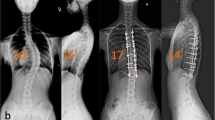

Twenty-six patients were included in this study with surgical correction by one surgeon between January 2014 and December 2017. Clinical data and radiographic images (preoperative, postoperative and one-year follow-up) were retrospectively analyzed and metal load, flexibility index, correction rate and correction index were consequently calculated. The Pearson correlation analysis was used for metal load—correction index and metal load—correction rate, correction of kyphosis—metal load and correction of lordosis—metal load. According to the mean metal load of 88%, patients were divided into two subgroups—a low-density group of 12 patients and a high-density group of 14 patients. Clinical and radiographic features were examined by an independent two-sided t-test.

A total of 62 surgical scoliosis treatments in one institution between January 2014 and December 2017 were retrospectively analyzed. Every operation was performed by the same senior surgeon. Each patient had to perform a preoperative magnetic resonance imaging of the whole spine to exclude malformations of the medulla, e.g., a tethered cord. Before the surgery, standardized posterior-anterior, lateral and left- and right-bending radiographs were carried out. Postoperative imaging control (posterior-anterior and lateral whole spine) was performed one week and one year after the surgery. The Cobb-angle measurement for each radiographic image was performed by two examiners in order to minimize the measurement error. After applying the exclusion criteria, which are listed below, a total of 26 patients could be included in this study.

By calculating the correction index, the dependency of the flexibility on the correction rate was excluded. Sagittal correction was calculated for kyphosis (T5–T12) and lordosis (L1–L5). These measurements and calculations were performed individually for every curve in the scoliotic deformity directly postoperative and at the one-year follow-up. Additionally, the patients were divided into a high-density and a low-density group according to the mean metal load (88%) and consequently compared.

In summary, 26 patients, with a mean age of 17.1 ± 3.26 years, were included in this study. Eight patients were male and 18 female, 10 patients had a neuromuscular and 16 an idiopathic scoliosis. Mean flexibility index was 34.7 ± 20.19%. The correction rate directly postoperative was 70.43 ± 13.79%. At the follow-up one year later, the correction rate was 67.90 ± 13.96%. The mean correction index was 3.40 ± 4.81 directly postoperative and 3.23 ± 4.47 at the follow-up.

Low-density group

This group included 12 patients with a mean age of 17.3 ± 3.09 years. The ratio male:female was 3:9, seven patients had an idiopathic and five a neuromuscular scoliosis. The mean Cobb-angle of the preoperative posterior-anterior radiograph was 62.6 ± 16.89°, of the convex bending radiograph 43.83 ± 19.11° and the mean flexibility index was 29.76 ± 19.11%. The average metal load was 81 ± 3.85% with 13.58 ± 2.36 instrumentation levels and 22.17 ± 4.63 pedicle screws. The mean operation time was 365.08 ± 48.69 min with a mean blood loss of 1162.86 ± 849.82 ml. Postoperative patients averagely had to stay 3.58 ± 3.85 days in the ICU and 0.33 ± 0.47 patients had a complication. In total numbers, four patients developed a complication. Three suffered from postoperative pneumonia and one patient had a urinary tract infection. Data for blood loss were only available for seven patients in this subgroup.

Directly postoperative, the mean Cobb-angle was 22.5 ± 12.95° with a correction rate of 65.82 ± 14.65% and a correction index of 4.42 ± 6.51. At the one-year follow-up, the average Cobb-angle was 23.11 ± 13.49°, the correction rate was 64.93 ± 15.43% and correction index 4.26 ± 6.063.

High-density group

The total number of patients in this group was 14; nine had an idiopathic and five a neuromuscular scoliosis. The ratio of male:female was 5:9, and the mean age was 16.9 ± 3.39. Preoperatively, the mean Cobb-angle was 66.3 ± 18.14°, the angle of the convex bending 45.93 ± 18.74° and the flexibility index was 40.13 ± 19.49%. The average instrumentation levels were 12.22 ± 3.09, with an average number of pedicle screws of 22.93 ± 5.89 and a mean metal load of 94 ± 5.08%. The mean operation time in minutes was 359 ± 90.21, the blood loss 670.83 ± 422.52 ml, the average ICU stay 4.21 ± 3.05 days and 0.29 ± 0.45 patients showed adverse events. Of the four complications detected in patients, three were due to pneumonia. One patient suffered from a haematothorax. In the CT scan, no screw misplacement was detected. The CT angiography showed no injury of a vessel, and the central venous catheter was in the right place. The patient did not need a thoracic drainage and no further intervention had to be performed. The amount of the perioperative blood loss in the high-density group was documented for twelve of the fourteen patients.

Immediately after the surgery, the mean Cobb-angle was 17.33 ± 10.82°, the correction rate was 75.04 ± 11.11% and the correction index 2.38 ± 1.28. One year after the surgery, the mean Cobb-angle was 20.28 ± 13.89°, the correction rate was 70.87 ± 11.59% and correction index was 2.20 ± 0.99.

Comparison between low- and high-density group

The only statistically significant difference between the high- and the low-density group was found in the correction rate directly postoperative (p = 0.047). At the one-year follow-up, no significant variance could be detected (p = 0.21).